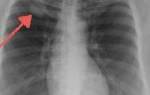

- Рентгенологическое исследование (лимфография);

- Лимфография. Относится к числу рентгенологических манипуляций. После введения окрашивающего вещества осуществляется серия снимков. Указанная процедура способствует изучению формы и количества лимфатических сосудов, степень их проходимости. Если в ходе исследования выявлена недоразвитость сосудов, диагностируют первичный лимфостаз. Вторичную патологию можно распознать по деформации сосудов, нарушению их ходов. Окрашивающее вещество в подобных случаях будет распространяться на подкожную клетчатку.

- Рентгенография грудной полости. Проводится в обязательном порядке при лимфостазе верхних конечностей.